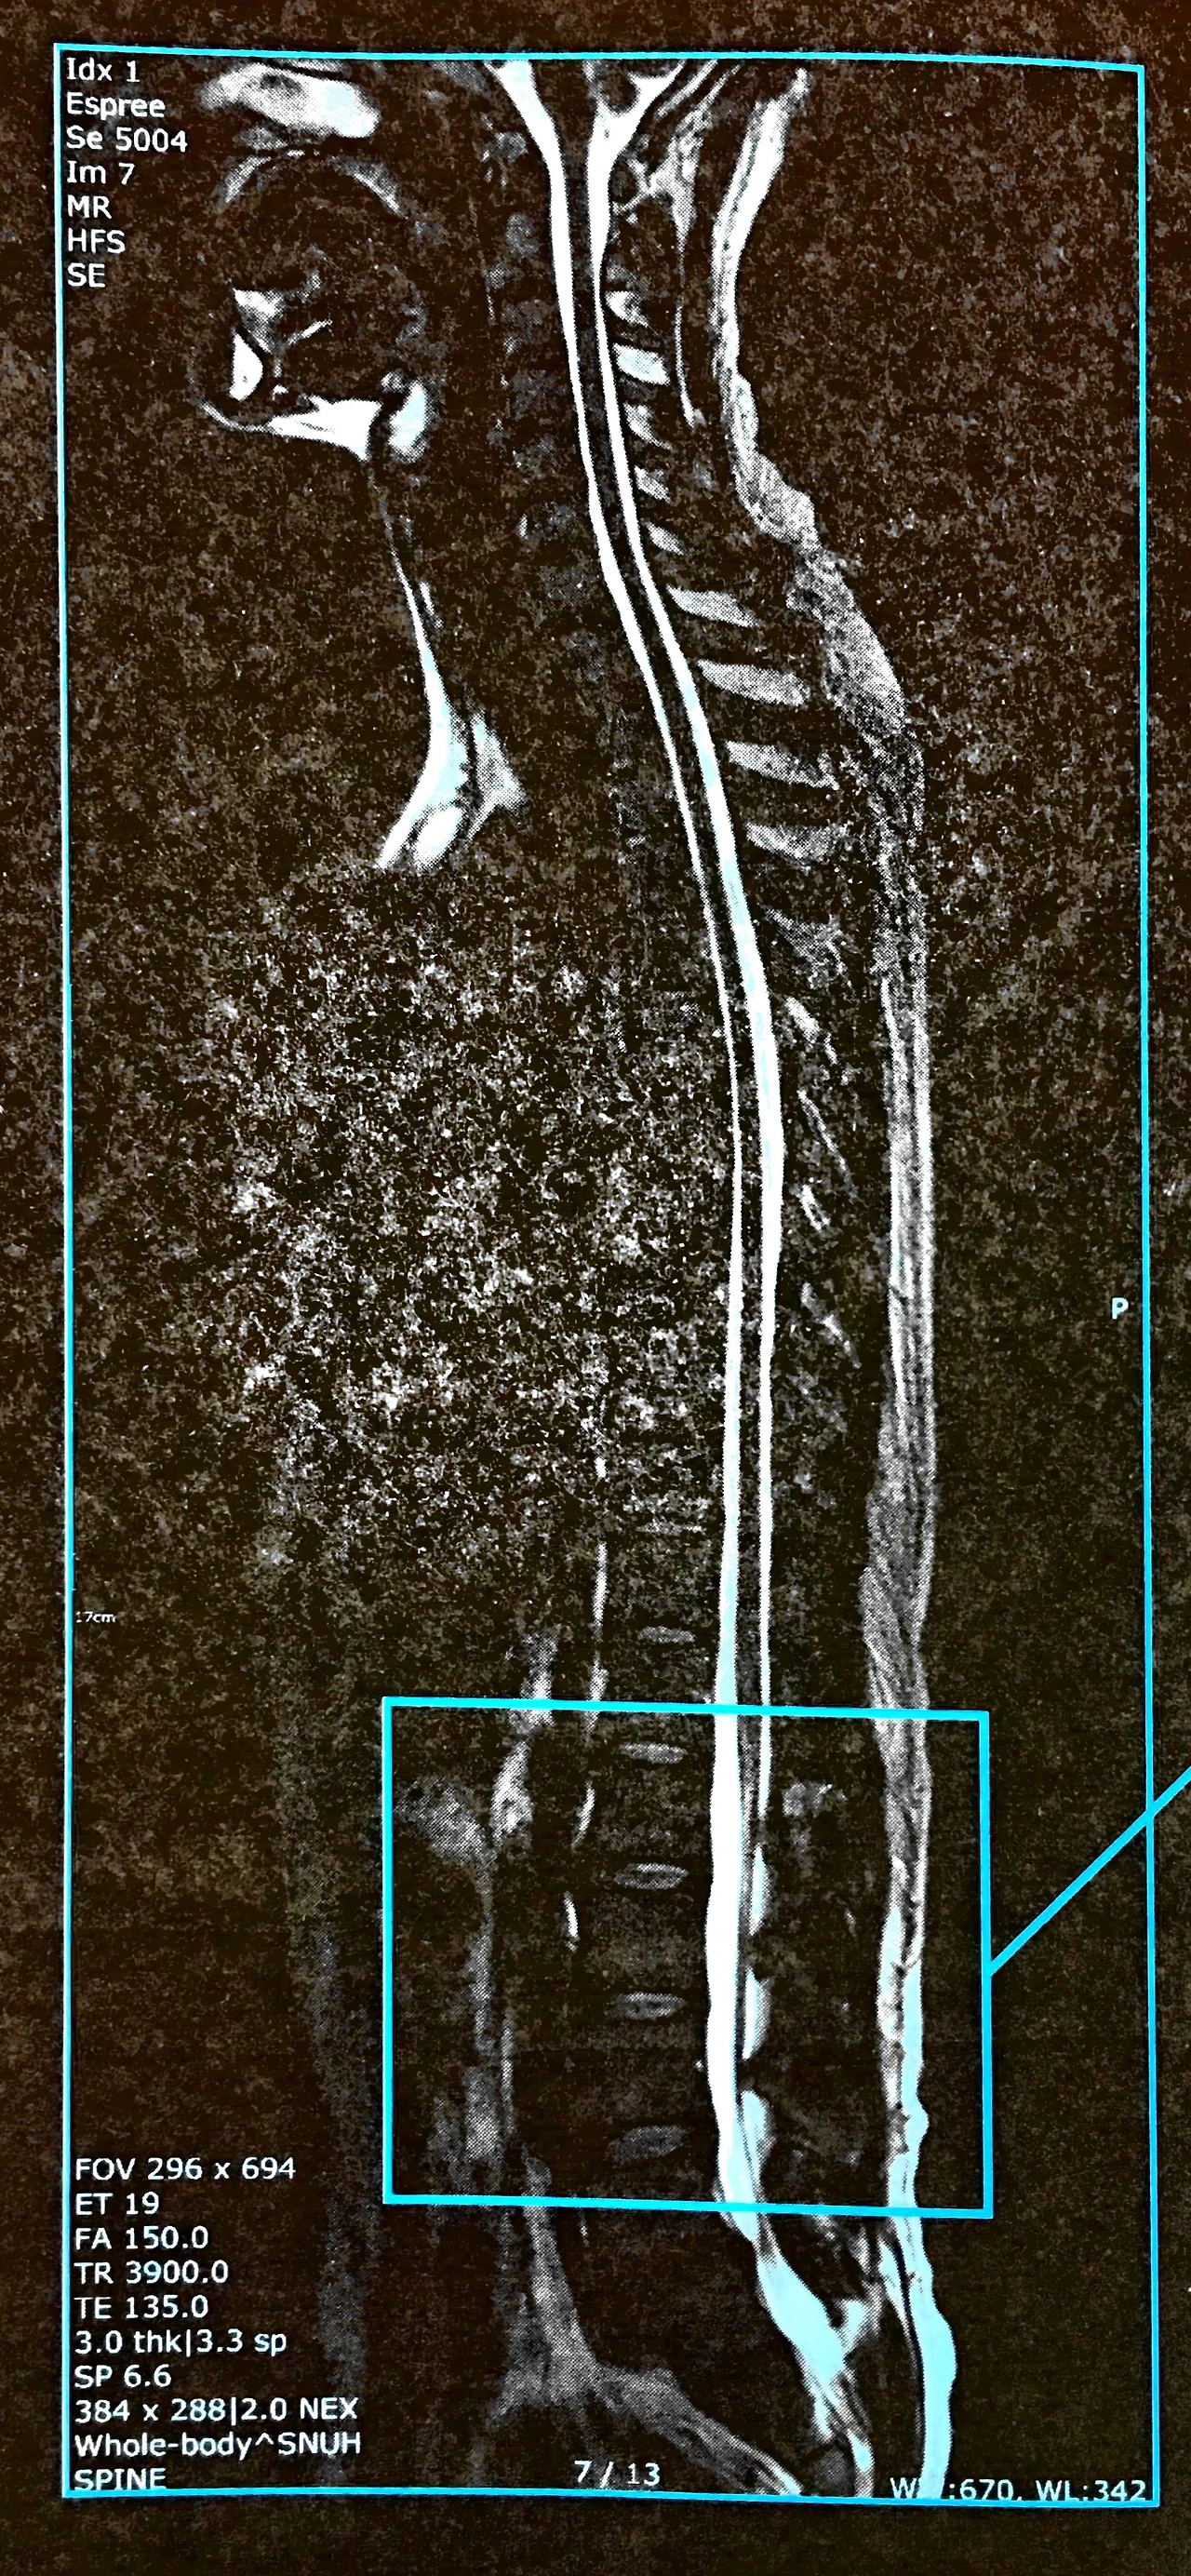

9. 디스크 손상의 종류는 어떤 것들이 있나?

backpain_01.JPG

backpain_03.JPG

backpain_02.JPG

backpain_04.JPG

backpain_06.JPG

backpain_05.JPG